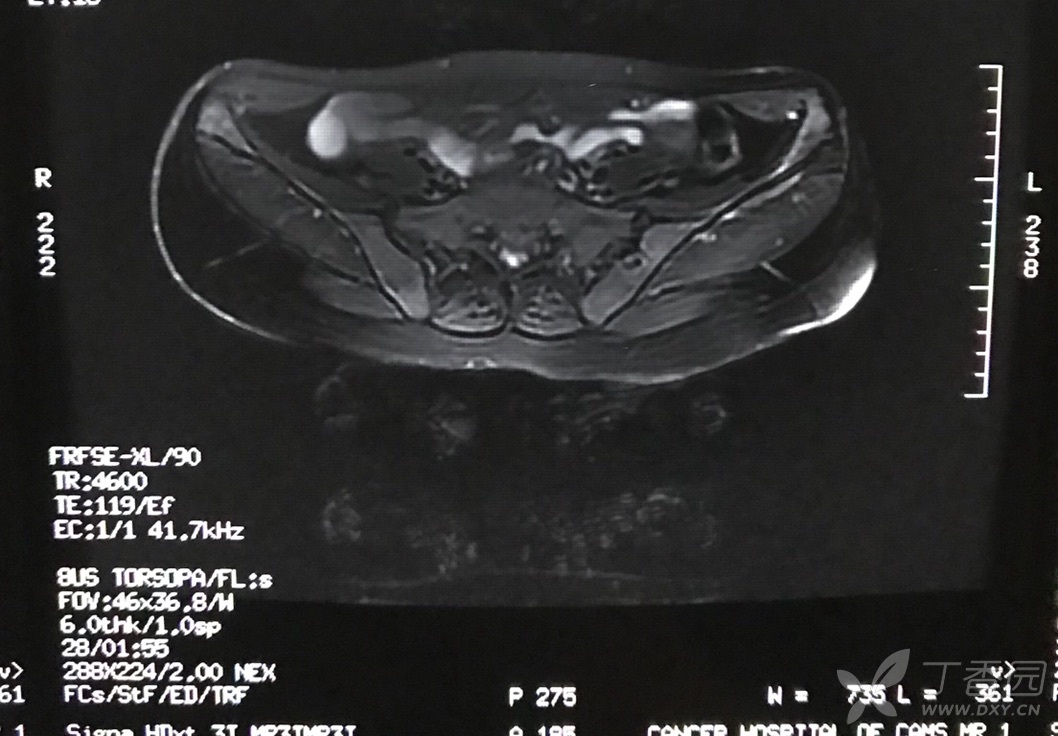

股骨头缺血性坏死解析 - 丁香园论坛